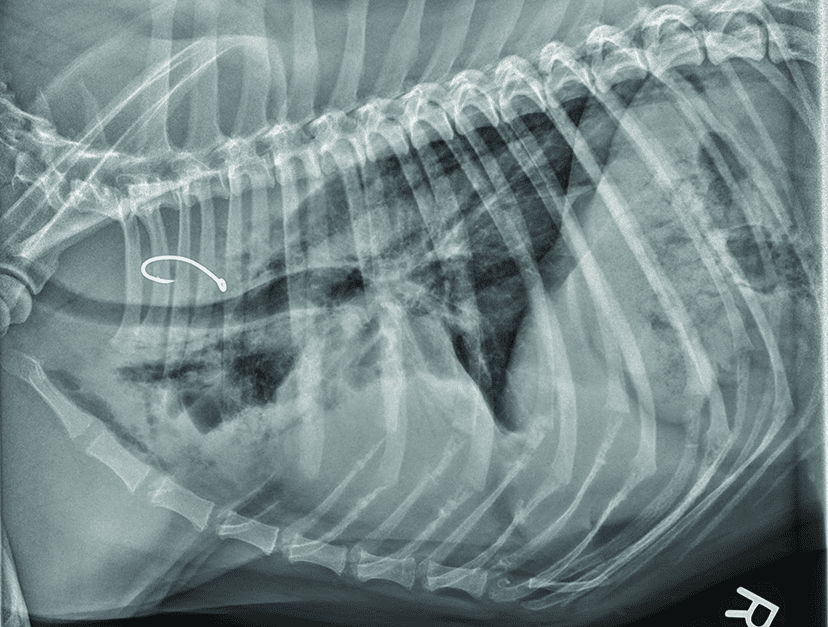

Treatment actually depends on the severity of the situation and whether your dog is able to swallow. If they can, then expect the veterinarian to “administer water or lubricate fluid” into a dog’s mouth so that it pulls the paper towel into the stomach. Other treatments may be as far as retrieving the paper towel using an endoscope device.